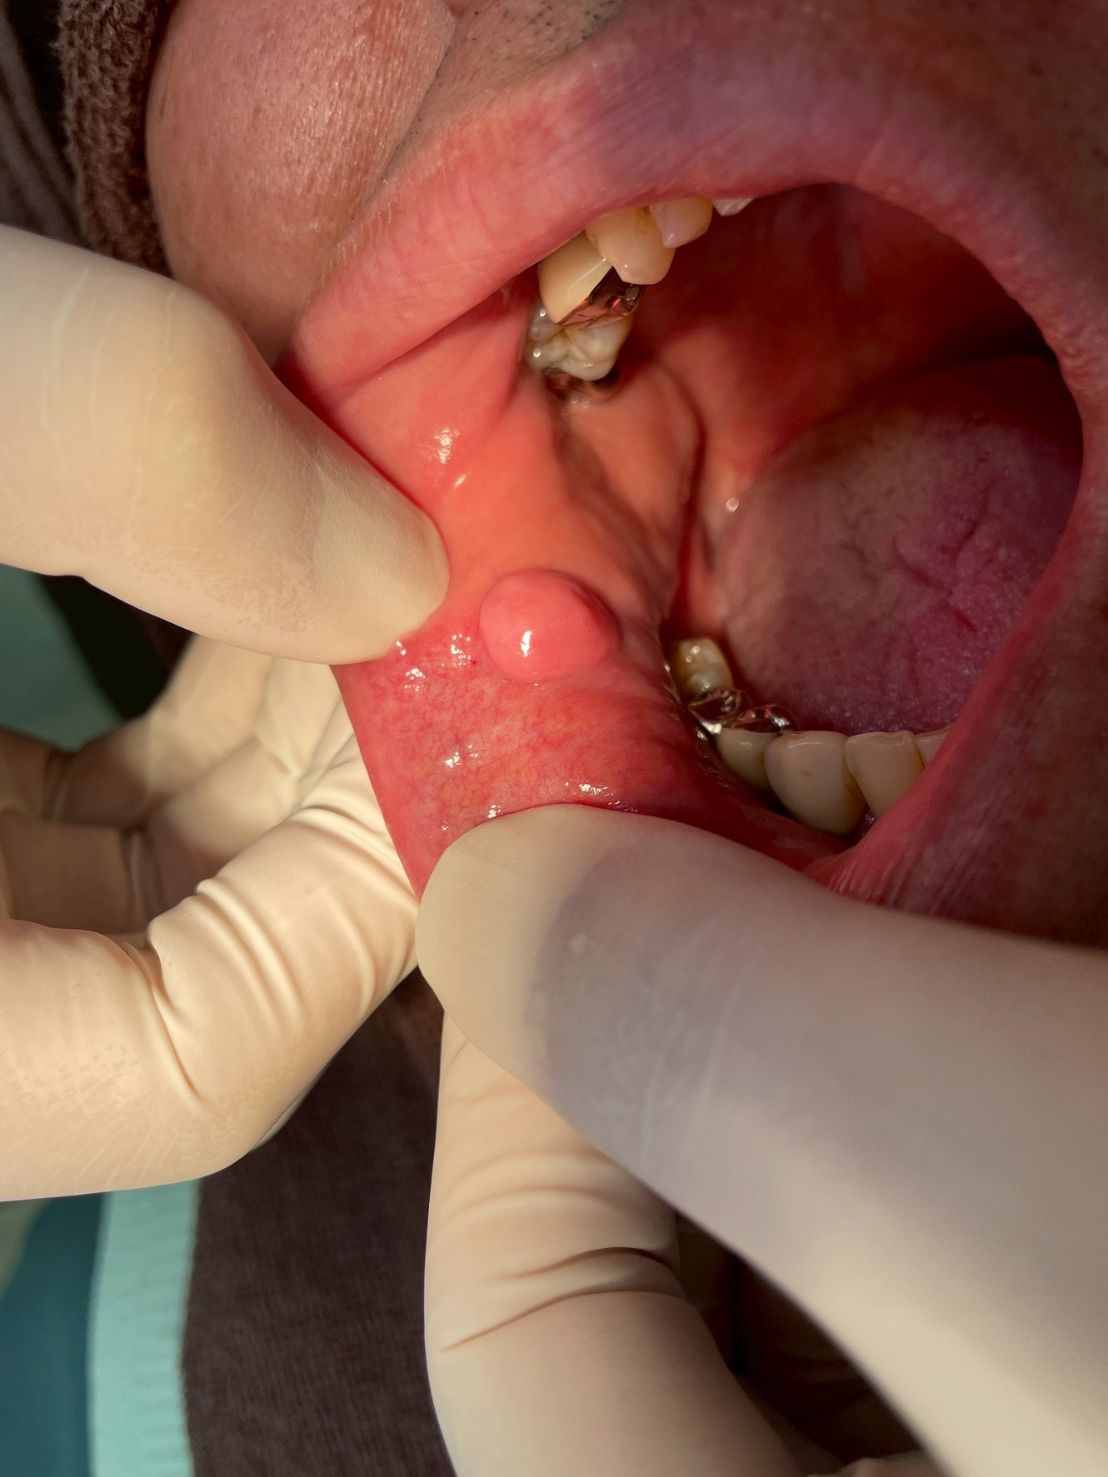

今回は、下唇の内側にできた「水ぶくれ」にお悩みの患者様の症例をご紹介します。

「口の中に水ぶくれのようなものができた」「一度潰れても、またすぐに膨らんでくる」という症状でご来院されました。

■症状の診断:小唾液腺粘液嚢胞(しょうだえきせんねんえきのうほう)

診断の結果、これは一般的に「粘液嚢胞(ねんえきのうほう)」と呼ばれるものでした。

唇や頬の内側にある「小唾液腺(唾液を作る小さな工場)」の出口が、誤って噛んでしまったり傷ついたりすることで詰まり、行き場を失った唾液が袋状に溜まってしまう病気です。